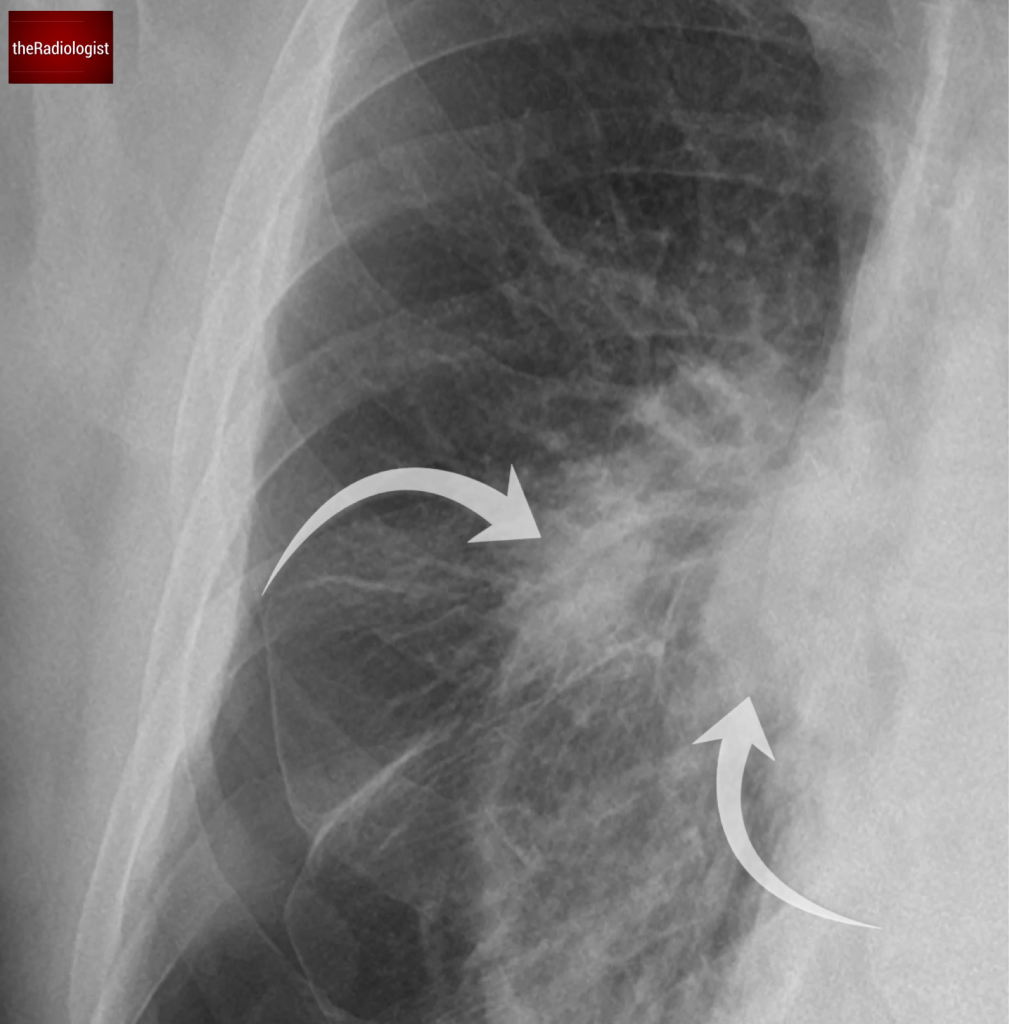

Going back to our case you will see a clear pleural line at the right lung apex whilst there is also a component at the right lung base, which is less commonly seen.

Did you spot the white pleural line both at the apex and within the right lower zone?

We can also see an air-fluid level at the right lung base – this represents a ‘hydropneumothorax’ ie there is both fluid and gas within the pleural space. Note how this appears slightly different to a standard pleural effusion where you get a ‘meniscus sign’ rather than a straight air-fluid level – this is because there is no surface tension from air in a hydropneuomothorax.

With a hydropneumothorax given the lack of surface tension we commonly see an air-fluid level rather than a meniscus sign that we see with a pleural effusion.

Now if we look at our case we can see the trachea and mediastinum are central meaning there is no tension pneumothorax.

In our case the trachea is in a normal position with no signs of shift to suggest shift in the context of tension. Note minor deviation of the trachea to the right at the level of the aortic arch is normal.